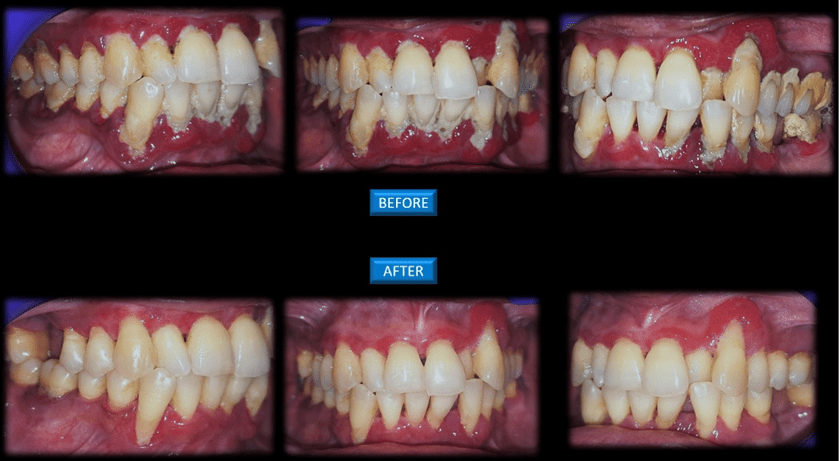

ADVANTAGES OF TEETH CLEANING:

- Regular cleaning can remove all the food debris, calculus, and plaque

- Prevents gingivitis and periodontitis

- Polishing can prevent further deposition

- Dental scaling is a professional cleaning of your teeth in which the plaque, calculus and the extrinsic stains can be removed from the surface of the teeth and also below the gumline

- The calculus can be either supragingival (above the gingival margin) or subgingival (below the gingival margin)

- Supragingival scaling will not be painful as the deposits will be above the gums

- Subgingival scaling will be done under local anaesthesia, as the deposits will be present below the level of gumline.

- Polishing will be done after scaling so that it prevents further deposition of the plaque and the calculus.